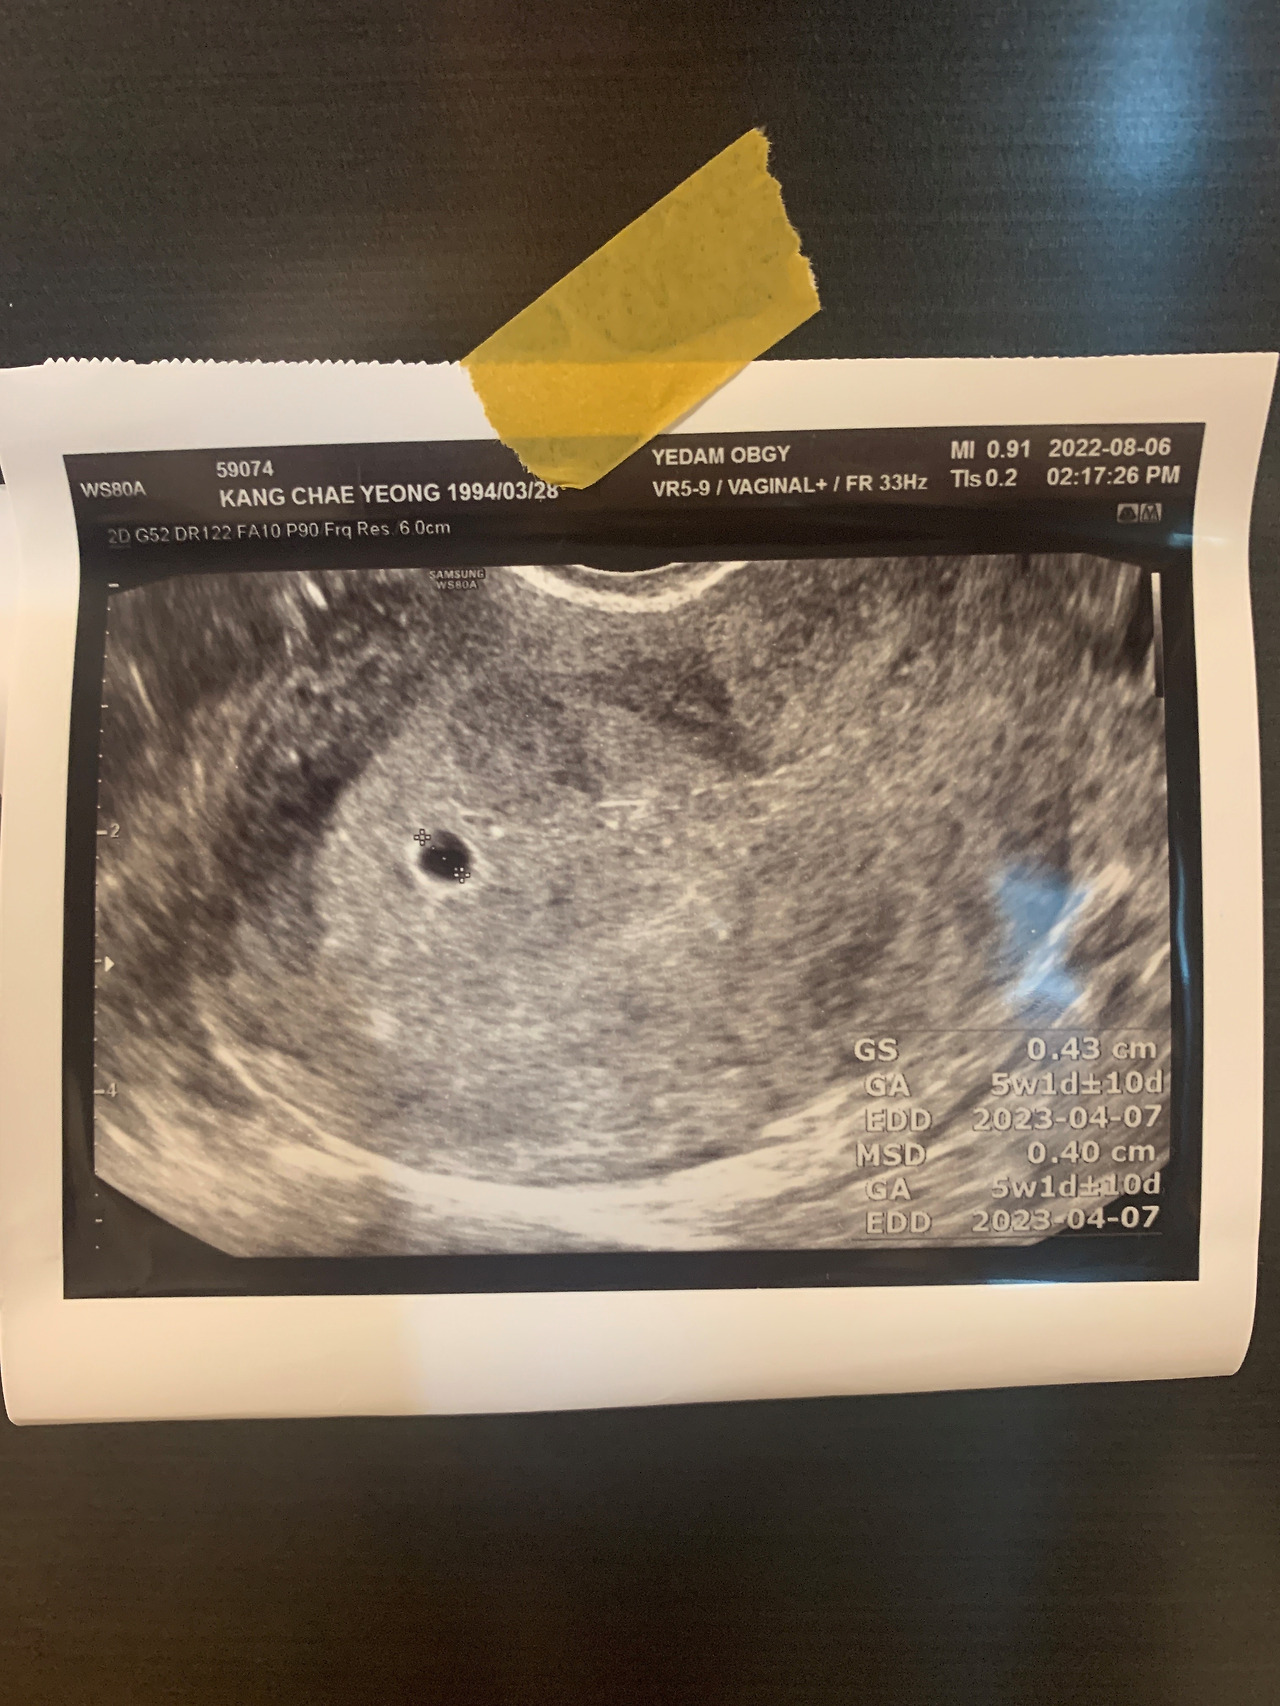

그리고 현재 우리 부부에게는 아이가 찾아왔다. 얼떨떨하고 아직은 이게 꿈인지 현실인지 분간이 되지 않는 날들의 연속이지만, 그래도 두려움보다는 행복과 기대가 더 크게 느껴지는 건 확실하다. 우리는 아직 경제적, 정신적으로 완벽히 준비되지 않았다. 하지만 완벽히라는 단어는 지극히 주관적이지 않을까. 재벌가 자식들처럼 경제적으로 풍족할 수는 없겠지만 적어도 가치관만큼은 건강하고 단단하게 키울 수 있겠다는 자신감, 이 정도라면 그래도 새로운 생명을 기다리는데 꽤 준비된 상태가 아닐까?

엄마랑 아빠가 잘 기다려볼게.

건강하게 오렴. 토실아